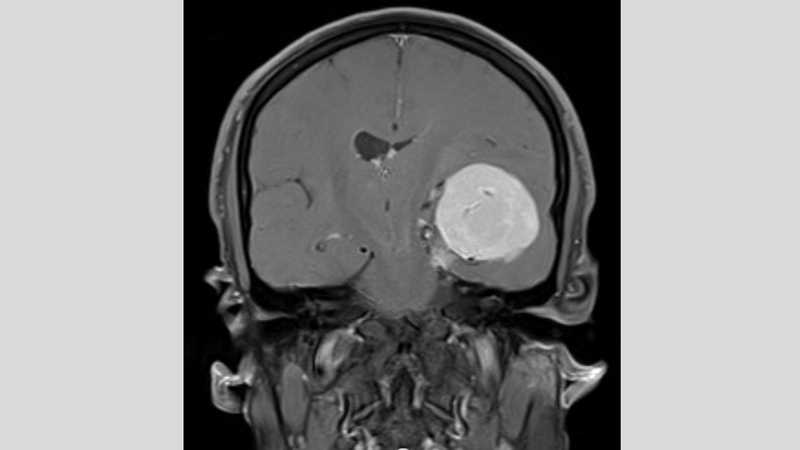

وبعد 10 سنوات، قرر (مهند) حجز موعد لإجراء تصوير بالرنين المغناطيسي، فبينت النتائج وجود ورم دماغي بحجم كرة بلياردو في الجانب الأيسر من الجمجمة، يضغط على الدماغ، فلجأ إلى مستشفى «كليفلاند كلينك أبوظبي»، حيث قرر الأطباء استئصال الورم.

واستغرقت عملية الاستئصال ثماني ساعات، وكانت معقدة جداً بسبب موقع الورم الكائن في قاعدة الجمجمة وضغطه على الدماغ، ووجود شبكة من الأوعية الدموية فيه. لذلك، استخدم الأطباء تقنية متطورة تُدعى «الملاحة العصبية»، التي تقوم بعملية مسح تفصيلية ثلاثية الأبعاد للدماغ للمساعدة في توجيه العمل الجراحي، وضمان إمكانية إزالة الورم دون الإضرار بأي من أنسجته السليمة المحيطة. وبالفعل خضع المريض للجراحة، وتمكن بعدها من التعافي والعودة إلى حياته العائلية والمهنية.

وقال أخصائي الجراحة العصبية في مستشفى كليفلاند كلينك أبوظبي، الدكتور محمد سامي الحمادي: «كان الورم في دماغ (مهند) من أكبر الأورام التي رأيتها لدى المرضى هنا في أبوظبي، فقد نما على مدى فترة طويلة، ما أتاح تشكّل شبكة أوعية خاصة به وتسبب في حدوث انتفاخ كبير أدى إلى دفع الدماغ لأكثر من سنتيمتر عن المركز. كان لابد من استئصال الورم، وإلّا لكان استمر بالنمو وأدى إلى تفاقم الأعراض».